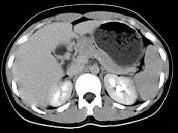

- 单项选择题结合图像,最可能的诊断为 ( )

A、胰腺癌

B、胰岛细胞癌

C、胰腺囊腺癌

D、胰腺炎

E、以上都不是